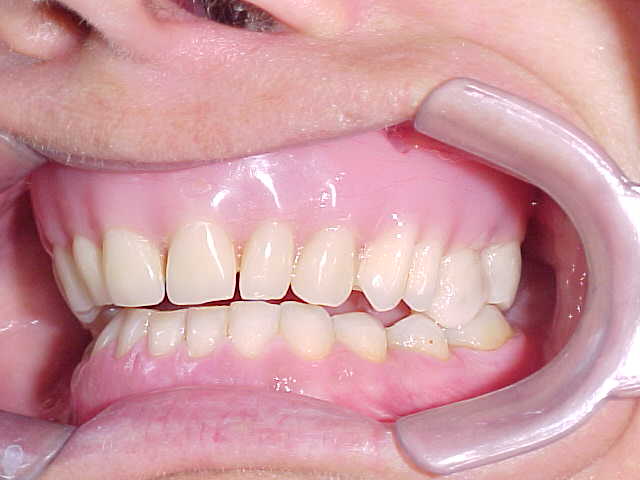

Diagnóstico preliminar das principais ocorrências: Prótese total na maxila em articulação com dentição natural inferior, apresentando acentuado trespasse horizontal (mordida profunda) e inclinações linguais generalizadas, com ausência do primeiro molar inferior esquerdo.

Confirmação da inclinação lingual generalizada em todos os elementos dentários